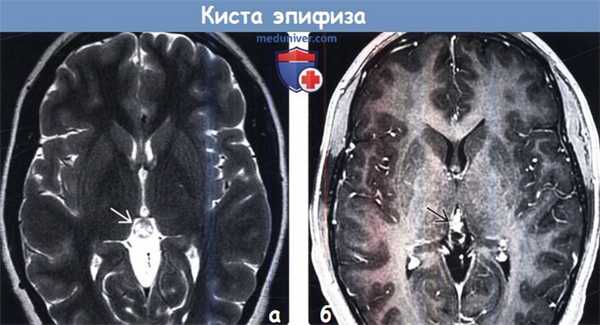

(а) МРТ, Т2-ВИ, аксиальный срез: у женщины 52 лет с головокружением и диплопией, но без неврологической симптоматики определяется эпифиз нормальных размеров, но с поликистозным внешним видом.

(б) МРТ, постконтрастное Т1-ВИ, режим подавления сигнала от жира: у этого же пациента наблюдается ободковый характер контрастирования эпифиза . Эпифизы с поликистозным характером строения являются вариантом нормы.4. Ангиография: